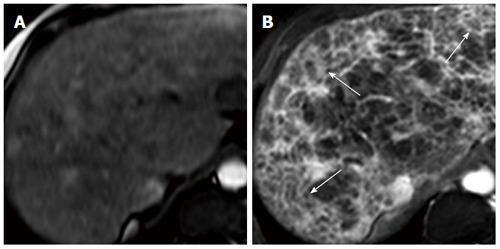

肝脂肪变性和肝纤维化:非侵入性评估

Hepatic steatosis and fibrosis: Non-invasive assessment.

Chronic liver disease is a major cause of morbidity and mortality worldwide and usually develops over many years, as a result of chronic inflammation and scarring, resulting in end-stage liver disease and its complications. The progression of disease is characterised by ongoing inflammation and consequent fibrosis, although hepatic steatosis is increasingly being recognised as an important pathological feature of disease, rather than being simply an innocent bystander. However, the current gold standard method of quantifying and staging liver disease, histological analysis by liver biopsy, has several limitations and can have associated morbidity and even mortality. Therefore, there is a clear need for safe and non-invasive assessment modalities to determine hepatic steatosis, inflammation and fibrosis. This review covers key mechanisms and the importance of fibrosis and steatosis in the progression of liver disease. We address non-invasive imaging and blood biomarker assessments that can be used as an alternative to information gained on liver biopsy.

摘要